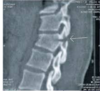

Espondilite anquilosante

Homens jovens, 3 década

Sacroileíte bilateral e simétrica

Coluna: Shiny corners (romanus): erosões nos cantos vertebrais com esclerose reativa;

vértebra quadrada (perda da concavidade anterior); espondilodiscite não infecciosa (lesão de andersson); aparência em bambu (anquilose dos sindesmófitos); sinal da faca (ossificação central - ligamento interespinhoso no rx ap),